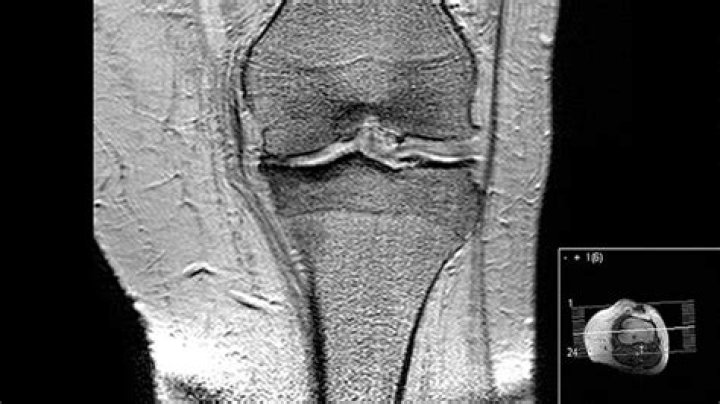

MRI is the most effective way to diagnose problems within any joint and the image sensitivity makes it the most accurate imaging tool available in detecting arthritis and other inflammatory changes. MRI is also a key diagnostic tool when patients have lower back pain, radiating pain or hip/groin pain.

MRI can clearly identify some of the signs of osteoarthritis, including whether cartilage is wearing away. MRI can also detect signs of rheumatoid arthritis, but a doctor will also use a variety of other tests, such as blood tests. Doctors can distinguish between soft tissues and fluids using MRI.

When examining an MRI, an orthopedist will typically look for the following structures, which may indicate osteoarthritis: damage to the cartilage. osteophytes, also called bone spurs. subchondral sclerosis, which is increased bone density or thickening in the subchondral layer of the joint.